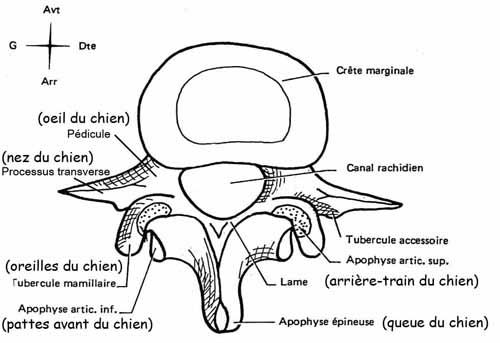

Tu peux analyser les lames sur le cliché de profil pour le rachis cervical, dorsal et lombaire ainsi que sur l’incidence de ¾ de lombaire où tu déroules les chiens de la chapelle

Les pédicules tu les analyses en coupe optique sur les incidences de face et sur le profil

Rachis cervical:  Rachis dorsal: Rachis dorsal:  Rachis lombaire: Rachis lombaire:   1. Processus articulaire supérieur 2. Pédicule droit 3. Processus transverse droit 4. Isthme 5. Processus articulaire inférieur 6. Lame opposée 7. Processus transverse opposé 8. Epineuse 9. Interligne articulaire postérieure 10. Processus articulaire inférieur opposé 11. Processus articulaire supérieur opposé Pour ce qui est de la radioanatomie; nous te laissons le soin d'apprendre tout cela grâce aux livres à ta disposition et à tes stages surtout!  Nous avions commencé une liste de livres de radiologie; à toi de t'en servir et bonnes recherches! Si tu souhaites trouver d'autres correspondances, si quelques détails t'interpellent n'hésite pas à poser des questions précises! Bon courage la marmotte!